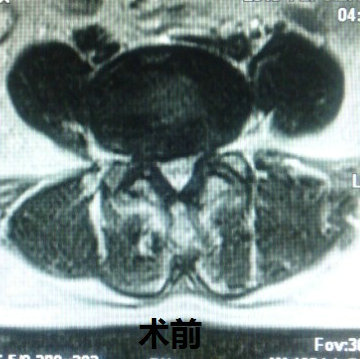

5.3mm椎间孔镜后...

德国进口椎间...